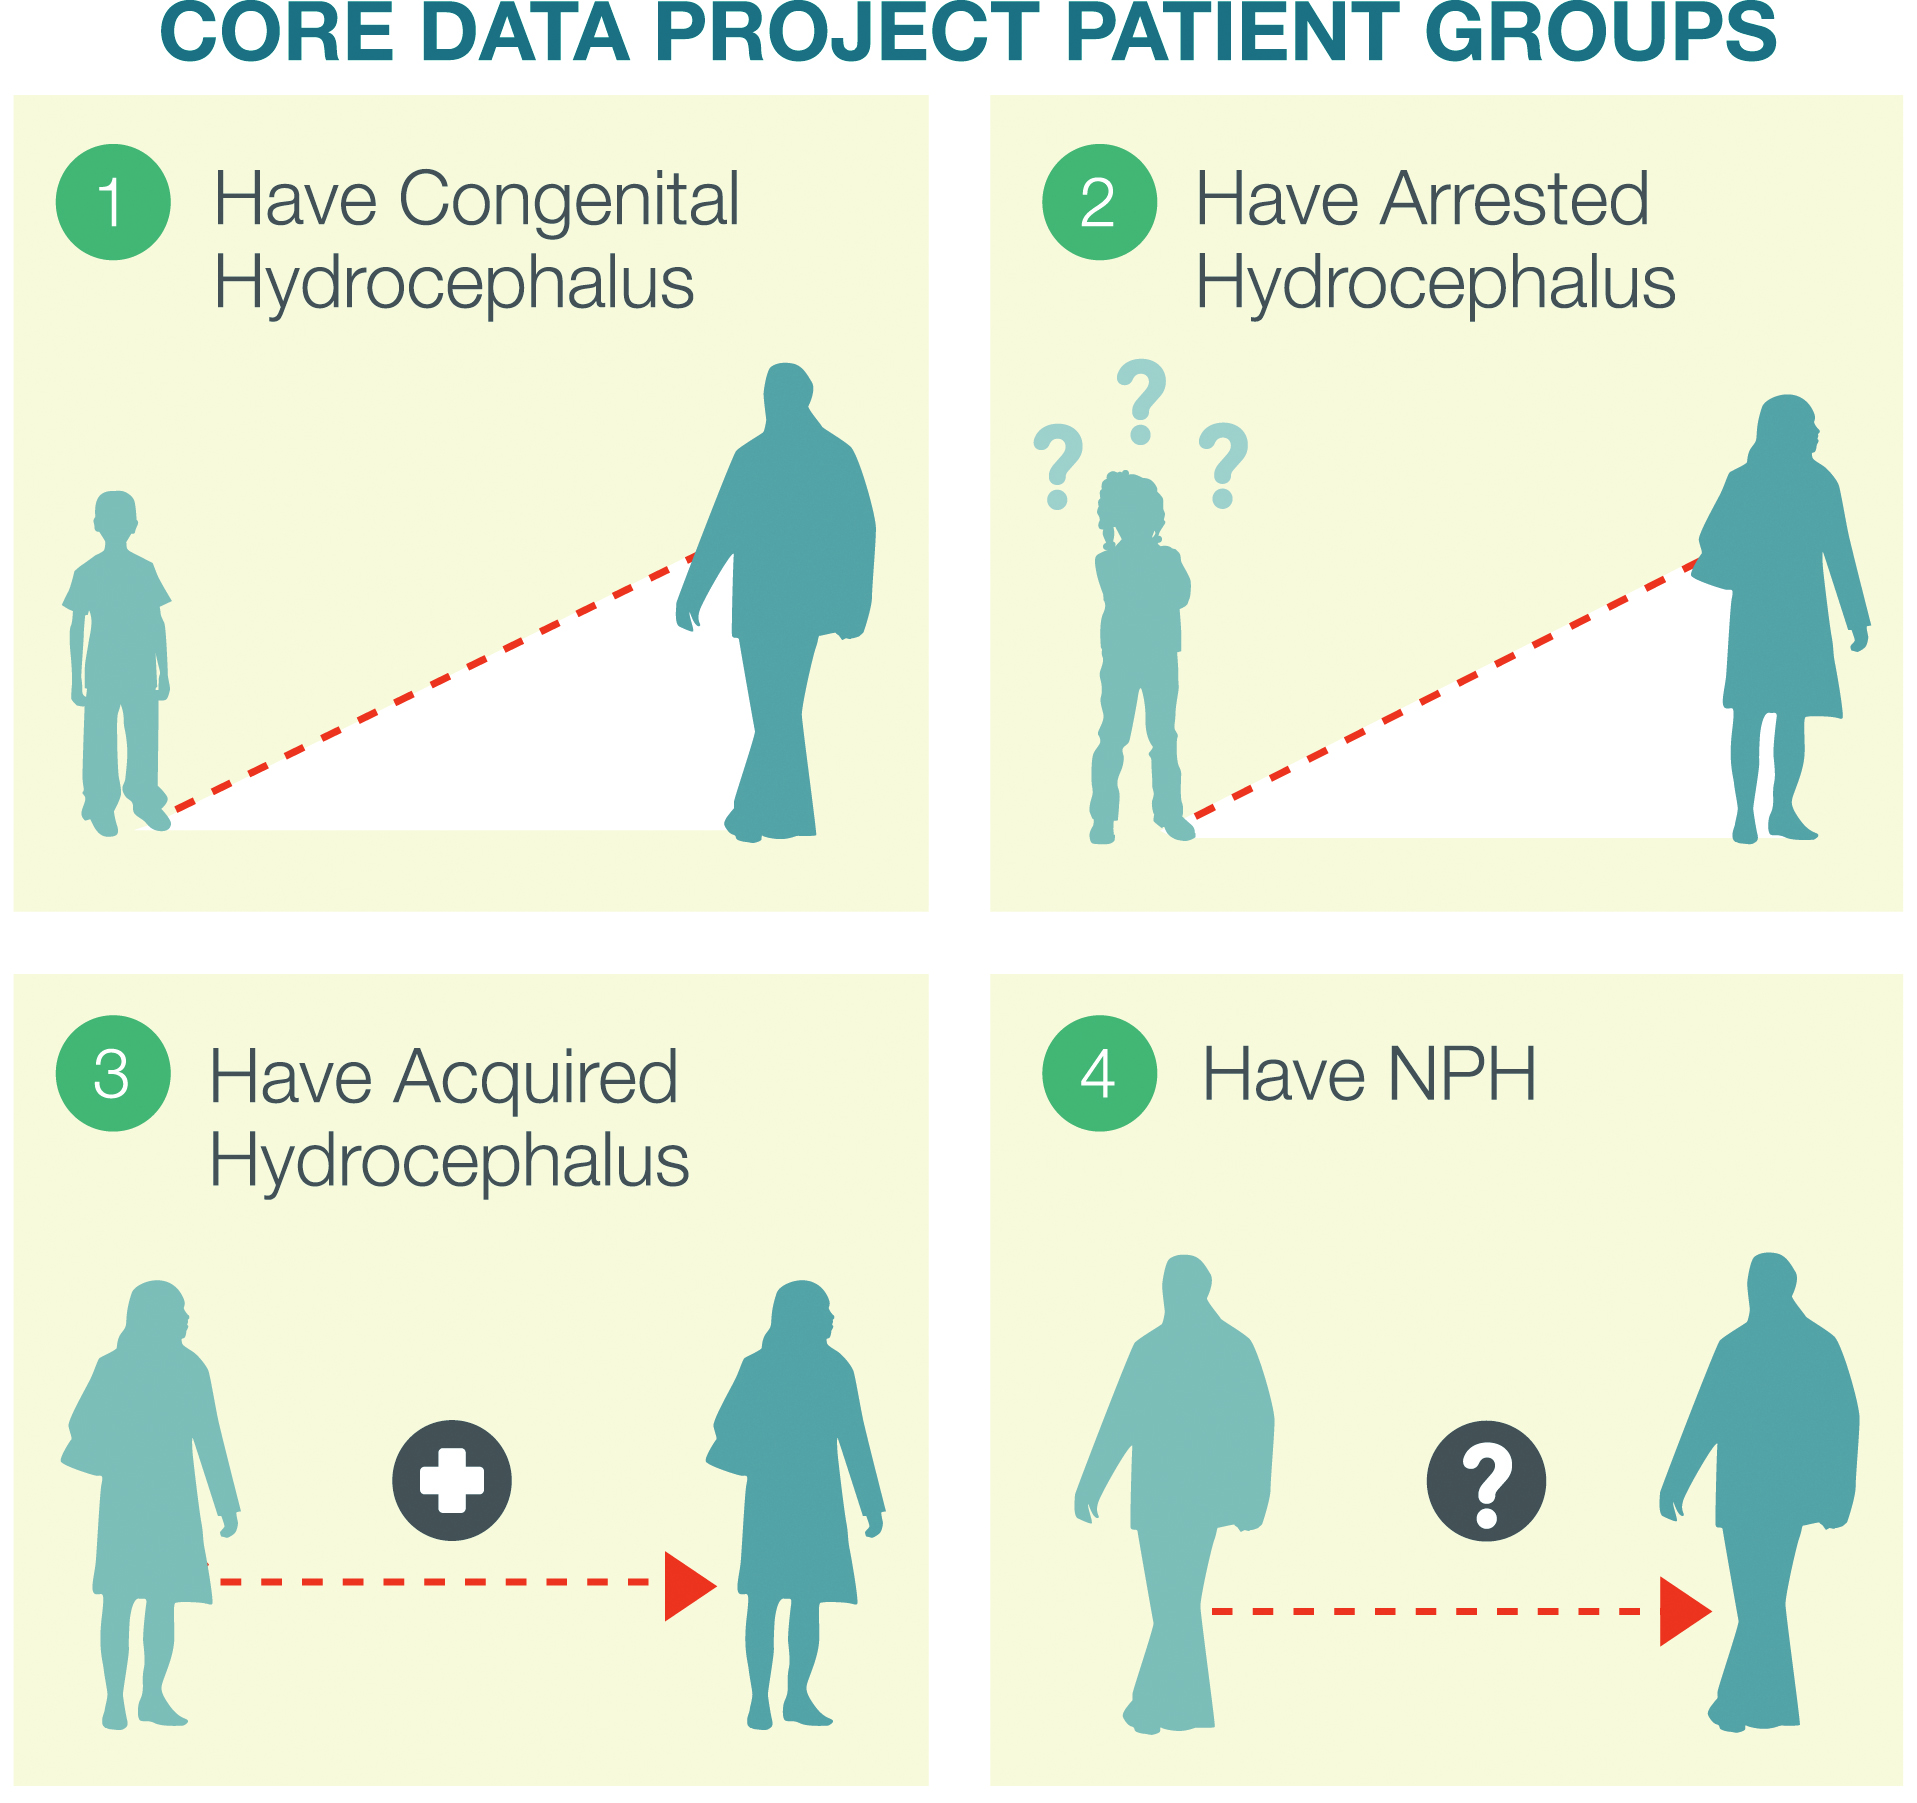

Adult Hydrocephalus Clinical Research Network | Research | Adult …

Schematic view of four different types of hydrocephalus described in …